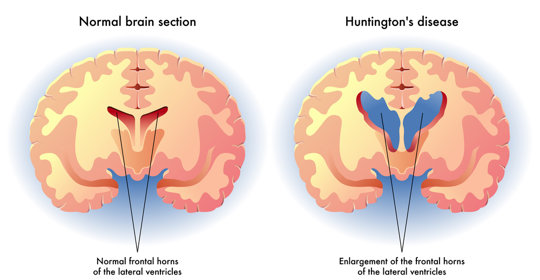

大腦與神經

腦外傷:症狀與處理方法

腦水腫:風險、治療與預防措施

腦水腫:處理方式與緊急性

腦外傷:症狀、處理與緊急醫療

腦積水:症狀、原因及處理方法

腦幹出血:顱內壓控制、生命支援、抗高血壓

腦幹出血:原因、症狀與治療

腦幹出血:原因與恢復

本文介紹了開顱手術後腦水腫的原因及恢復注意事項。

腦幹出血:前兆與應對

腦外傷:意識障礙、瞳孔異常、嘔吐、眩暈、呼吸不規則

腦幹出血:清醒機率與前兆

腦死:昏迷與聲音感知缺失

腦幹出血:後遺症、症狀及治療

腦幹出血:症狀、嚴重性與後遺症

腦水腫:症狀、後遺症、腦積水與手術治療

腦缺氧:吸氧療法、體位調整、高壓氧療